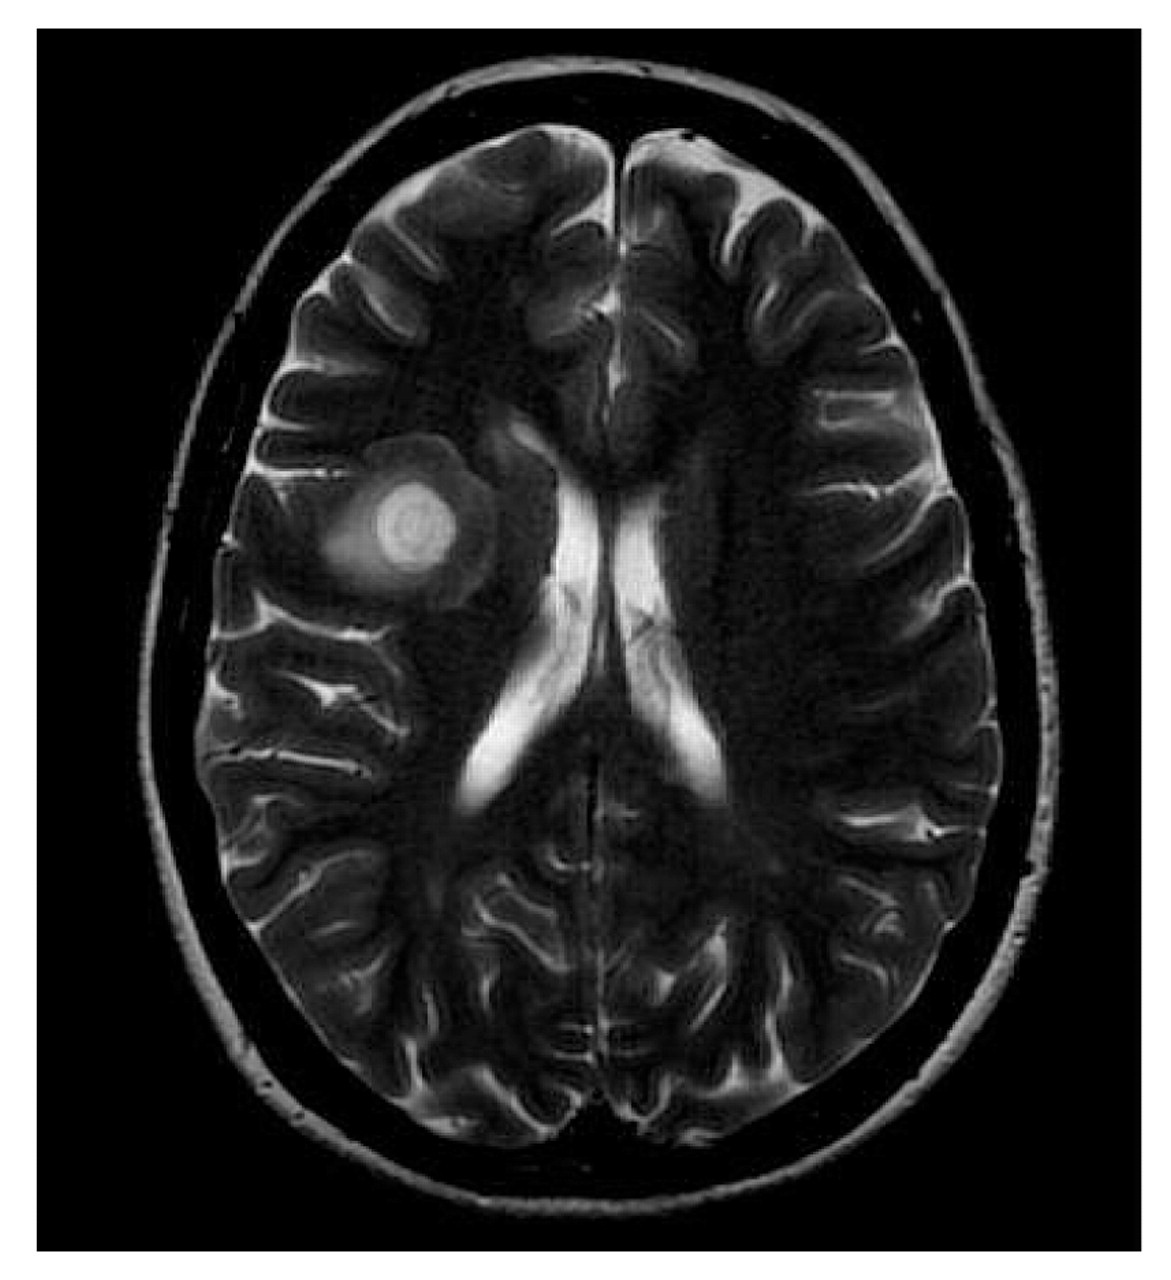

The laboratory tests ordered for hematologic, metabolic, and liver function testing had normal results. The rapid plasma regain test was nonreactive, and results of the antinuclear antibody test and serologic testing for Lyme disease were normal. The patient's vitamin B12 level and erythrocyte sedimentation rate were also normal. The MRI ordered at initial presentation and performed the same day showed a concentric lesion with alternating hypoand hyperintense rings corresponding to bands of myelinated and demyelinated tissue, respectively. The concentric patterns seen on MRI resemble the rings of a tree and thus give Balò disease it's hallmark appearance. Given the patient's presentation, her family history of MS, and the pathognomic concentric pattern seen on the MRI results13 (Figure 1 and Figure 2A), it was determined that Balò disease was the most likely diagnosis; this diagnosis was later confirmed by physicians at the Johns Hopkins Hospital, where she went for a second opinion.

Pathognomonic brain magnetic resonance imaging findings in a 30-year-old woman with Balò disease. T2-weighted axial image obtained at admission shows alternating concentric zones of demyelinated and myelinated white matter in the right frontal region, consistent with a diagnosis of Balò disease.